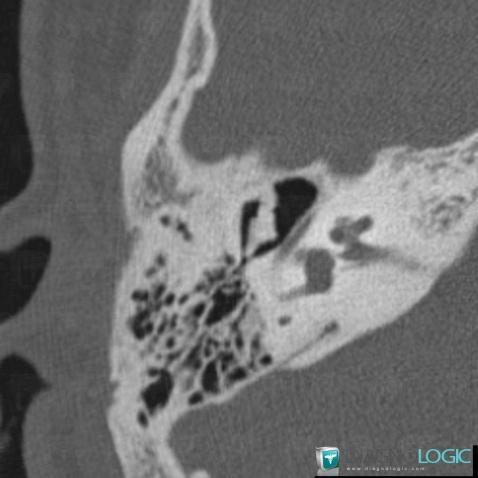

Minor aplasia, Middle ear, CT

- Diagnosis Minor aplasia, Location(s) Middle ear, with gamuts